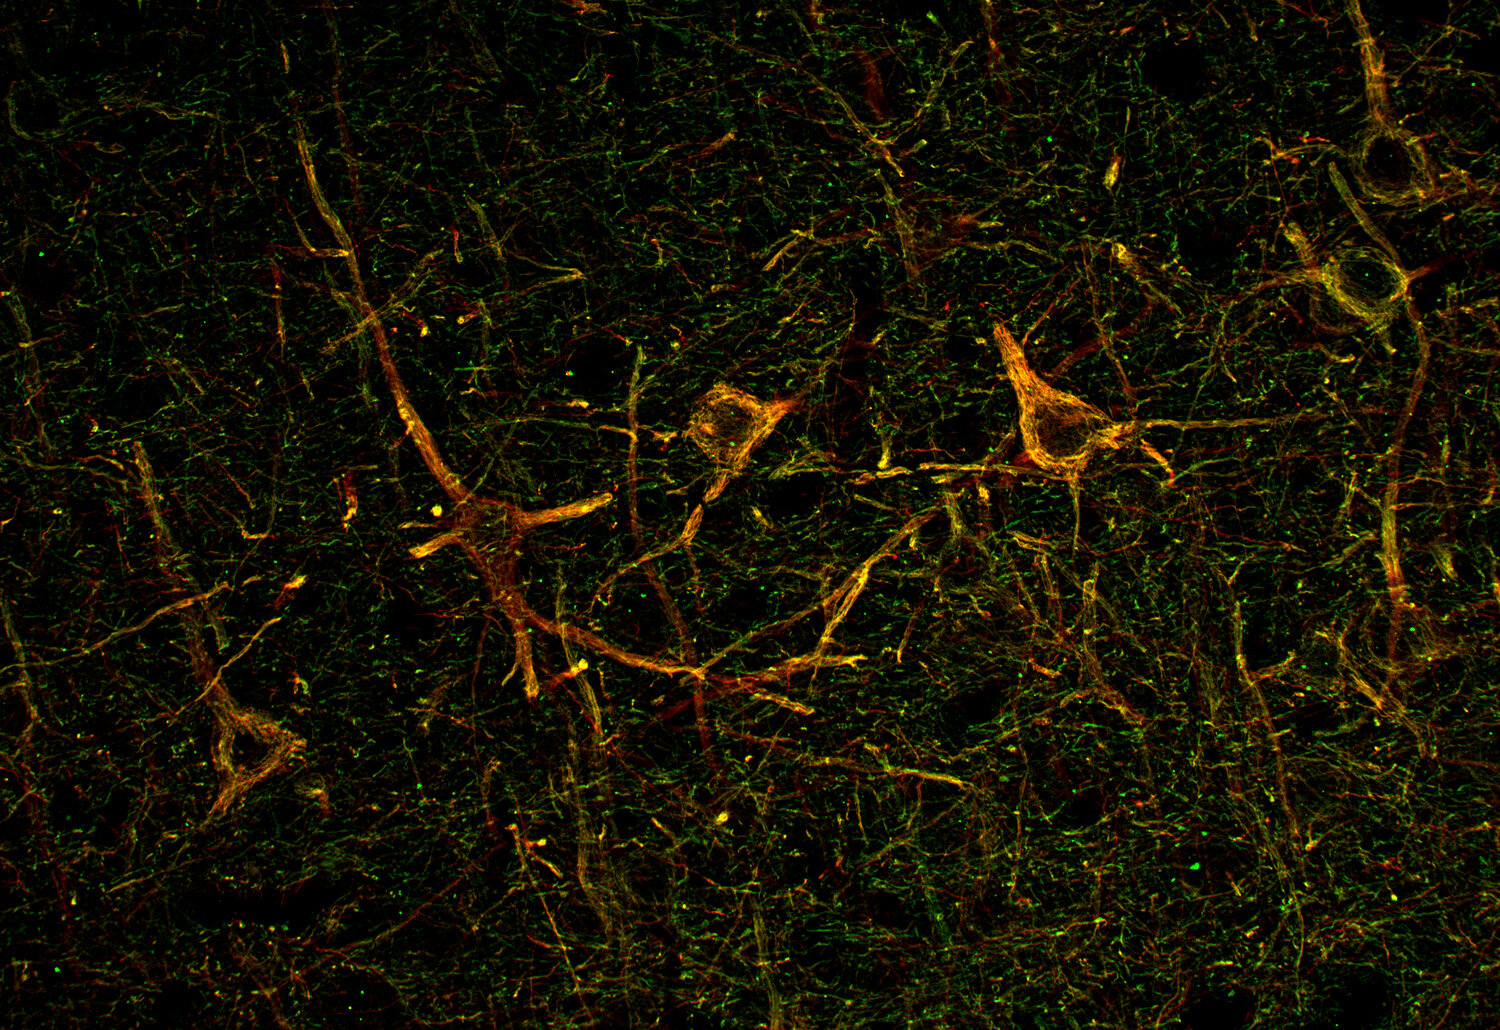

Neurofilament H antibody - 171 138

ICC: 1 : 500 up to 1 : 1000 gallery

IHC: 1 : 500 up to 1 : 1000 gallery

IHC-P (FFPE): 1 : 1000 up to 1 : 5000 gallery

IHC-Fr: 1 : 500 gallery

Neurofilaments (NFs) are intermediate filaments essential for providing structural support to neurons, particularly within axons. They play a crucial role in maintaining axonal diameter, which directly influences nerve conduction velocity (1). Neurofilaments are composed of three primary subunits - NF-L (light), NF-M (medium) and NF-H (heavy) – along with an NF-associated protein. In the adult central nervous system (CNS), α-internexin serves as the fourth neurofilament subunit, whereas in the peripheral nervous system (PNS), peripherin takes on this role (2).

Beyond their structural function, neurofilaments are also valuable biomarkers in both research and clinical settings. They are widely used in immunohistochemistry to stain and visualize axons, particularly in peripheral nerves and the CNS. Increased levels of neurofilament proteins in cerebrospinal fluid (CSF) or blood are strongly associated with neurodegenerative diseases, such as amyotrophic lateral sclerosis (ALS), multiple sclerosis (MS), and Alzheimer’s disease (3). In peripheral nerve studies, neurofilament staining is often combined with other markers, such as S100, to provide a more comprehensive assessment of nerve structure and pathology (4).